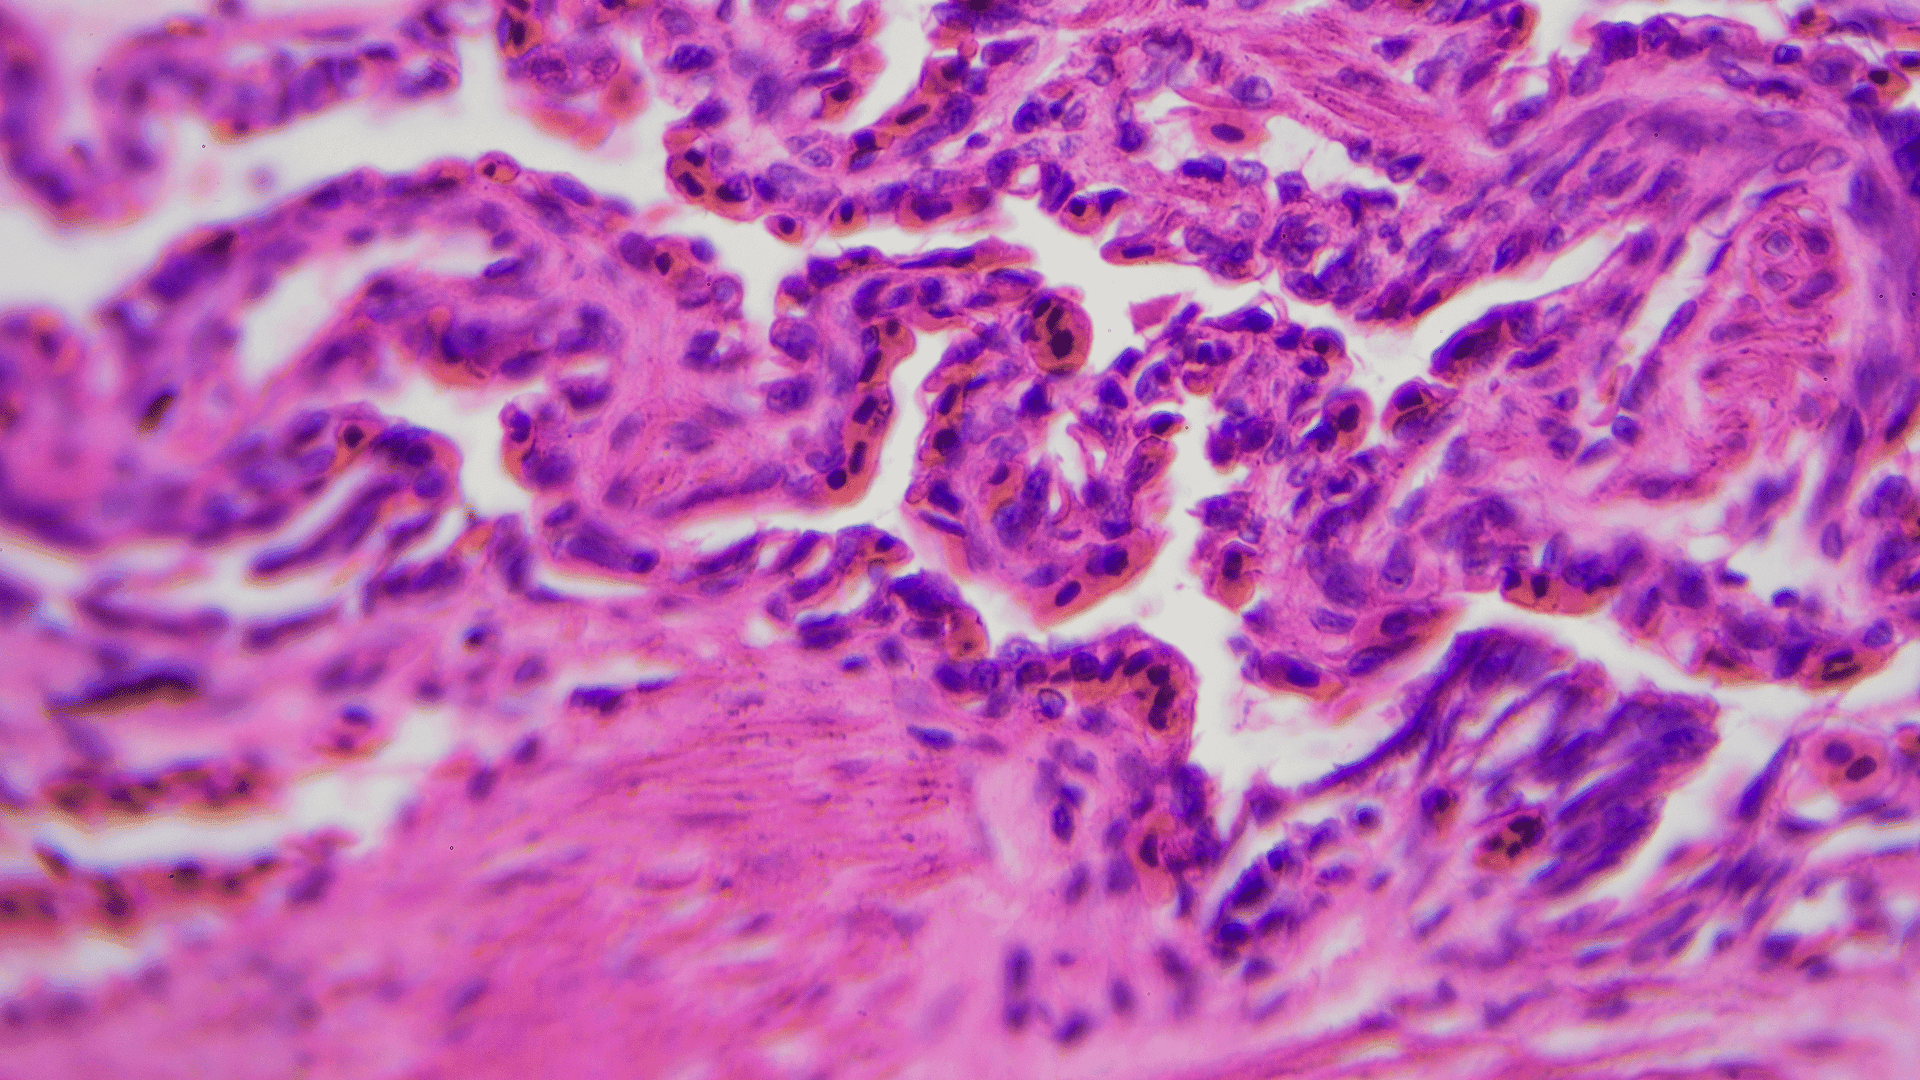

Diagnostyka chorób błony śluzowej jamy ustnej korzysta z nowoczesnych technologii, które umożliwiają dokładne zbadanie stanu śluzówki i wczesne wykrycie niepokojących zmian. Do najważniejszych narzędzi należą wizualizacja za pomocą zaawansowanych systemów optycznych i kamery wewnątrzustne, które dostarczają wyraźnych obrazów zmienionych obszarów. Biopsja i badania histopatologiczne to kolejne kluczowe metody, pozwalające na dokładną ocenę charakteru zmian. Nowoczesne techniki obrazowania, takie jak tomografia komputerowa i rezonans magnetyczny, również mogą być stosowane w szczególnych przypadkach.